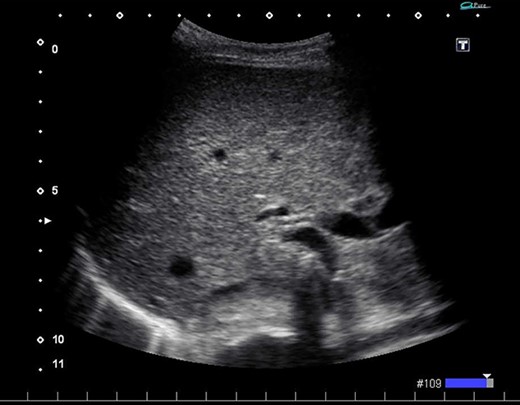

We found a gangrenous gallbladder with 180° clockwise rotation along the longitudinal axis and performed cholecystectomy (Fig. 3). Intraoperative exploration revealed no ischemic findings in other visceral organs. On US obtained immediately after the operation, the hyperechogenic foci disappeared (Fig. 4). Her postoperative course was uneventful, and she was transferred to the rehabilitation hospital on the 12th day. Histology confirmed a necrotic gallbladder without neoplastic changes.

Ultrasonography after surgery shows no findings of PVG in the liver.

In the present case, US revealed tiny pockets of gas that disappeared immediately after surgery. Chevallier et al. reported that US might have higher detectability than CT [10]. In general, PVGs are said to be distributed in accordance with gravity and gather at the surface of the liver [11]. However, the gas in the current case was detected around the hepatic hilum. This may be because cystic veins usually drain to the portal venous system via intrahepatic portal branches of segments 4 and 5 [12]. In cases of gallbladder disease, PVG can appear around the hepatic hilum instead of at the liver surface, which might be a useful finding when differentiating the condition from bowel ischemia.